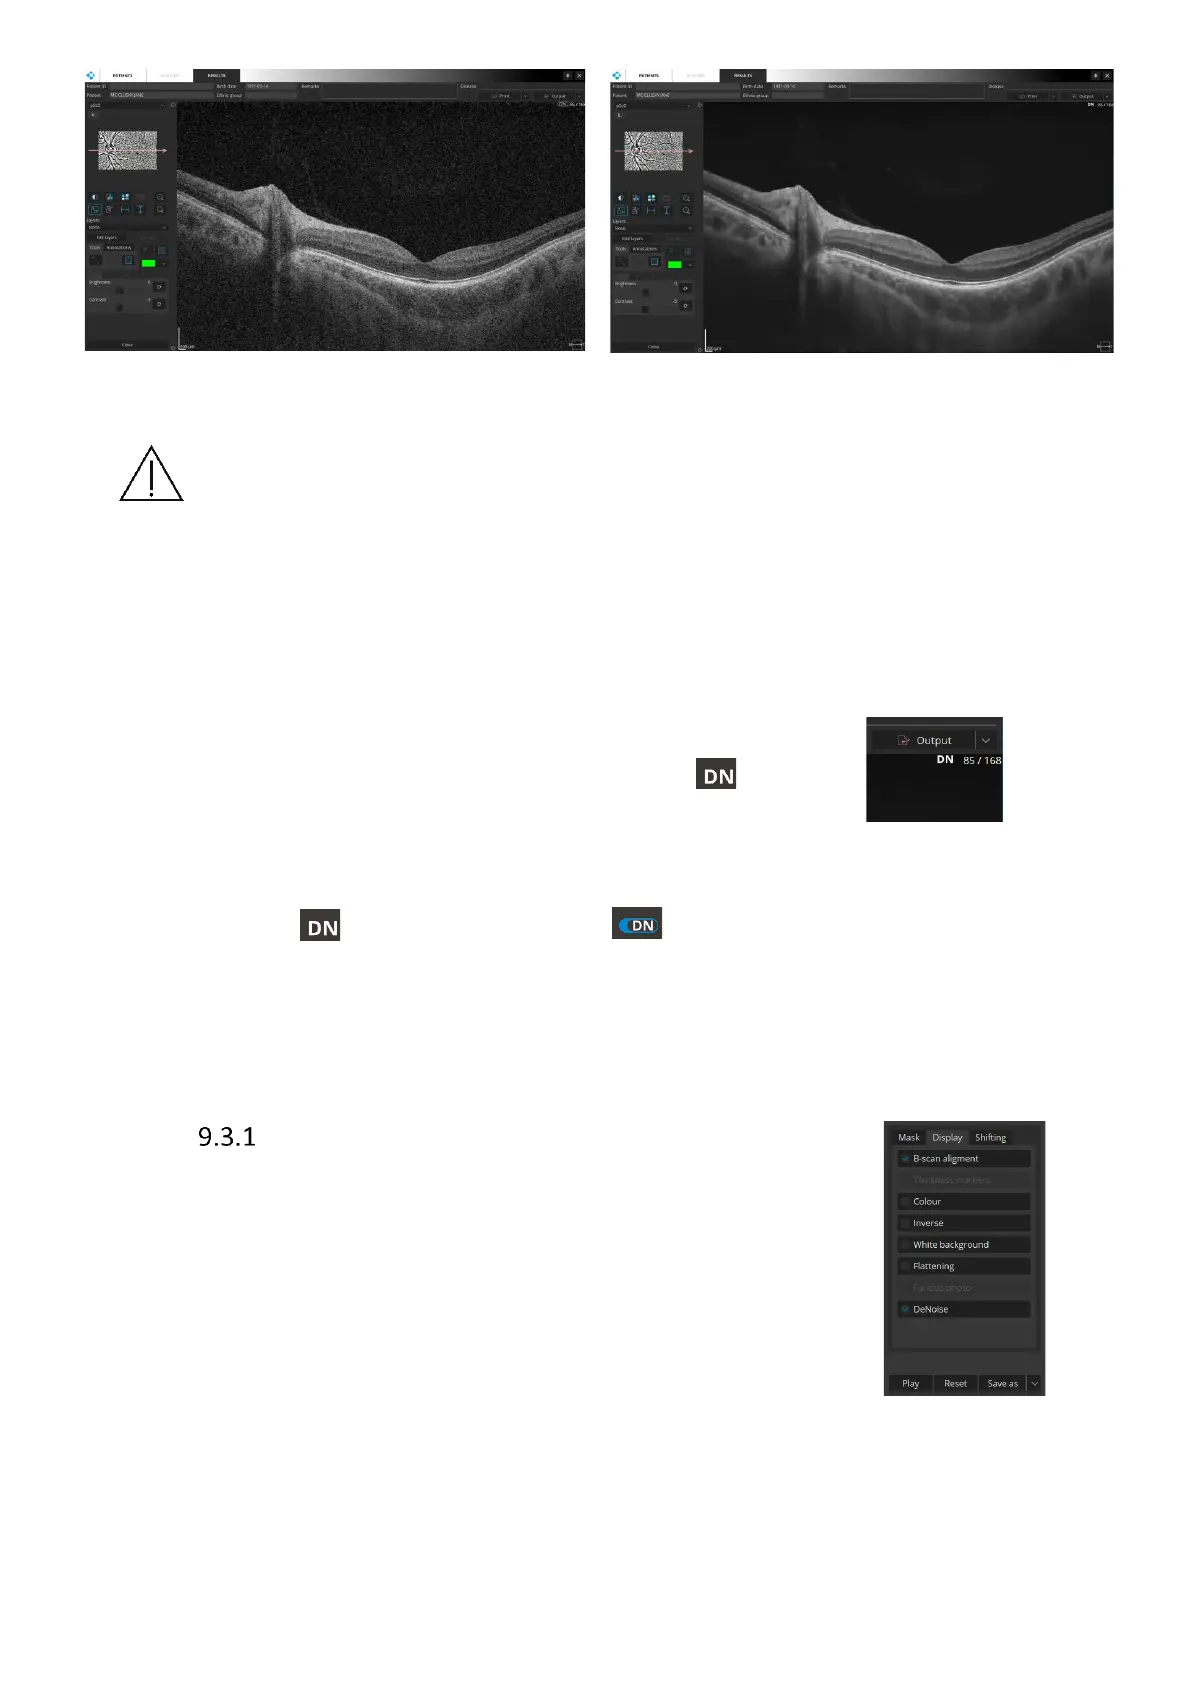

CAUTION The AI DeNoise algorithm works to enhance the visibility of morphological

structures by processing the original image. However, tomograms with very low

signal level or low QI may be challenging to be processed correctly. When working

with such tomograms it is recommended that the user always compares the denoised

image with the unprocessed image to make sure there is no variance between

morphological structures presented on both tomograms.

Turning AI DeNoise on and off

When the AI DeNoise function is on it is indicated by the sign in

the upper right-hand corner of the tomogram.

You can always turn the function off and go back to the original image. To do that hover your

mouse over the sign. It will change into the switch for you to click the function off.

Clicking the switch again turns the function back on.

Figure 87. AI DeNoise off (left) and on (right)